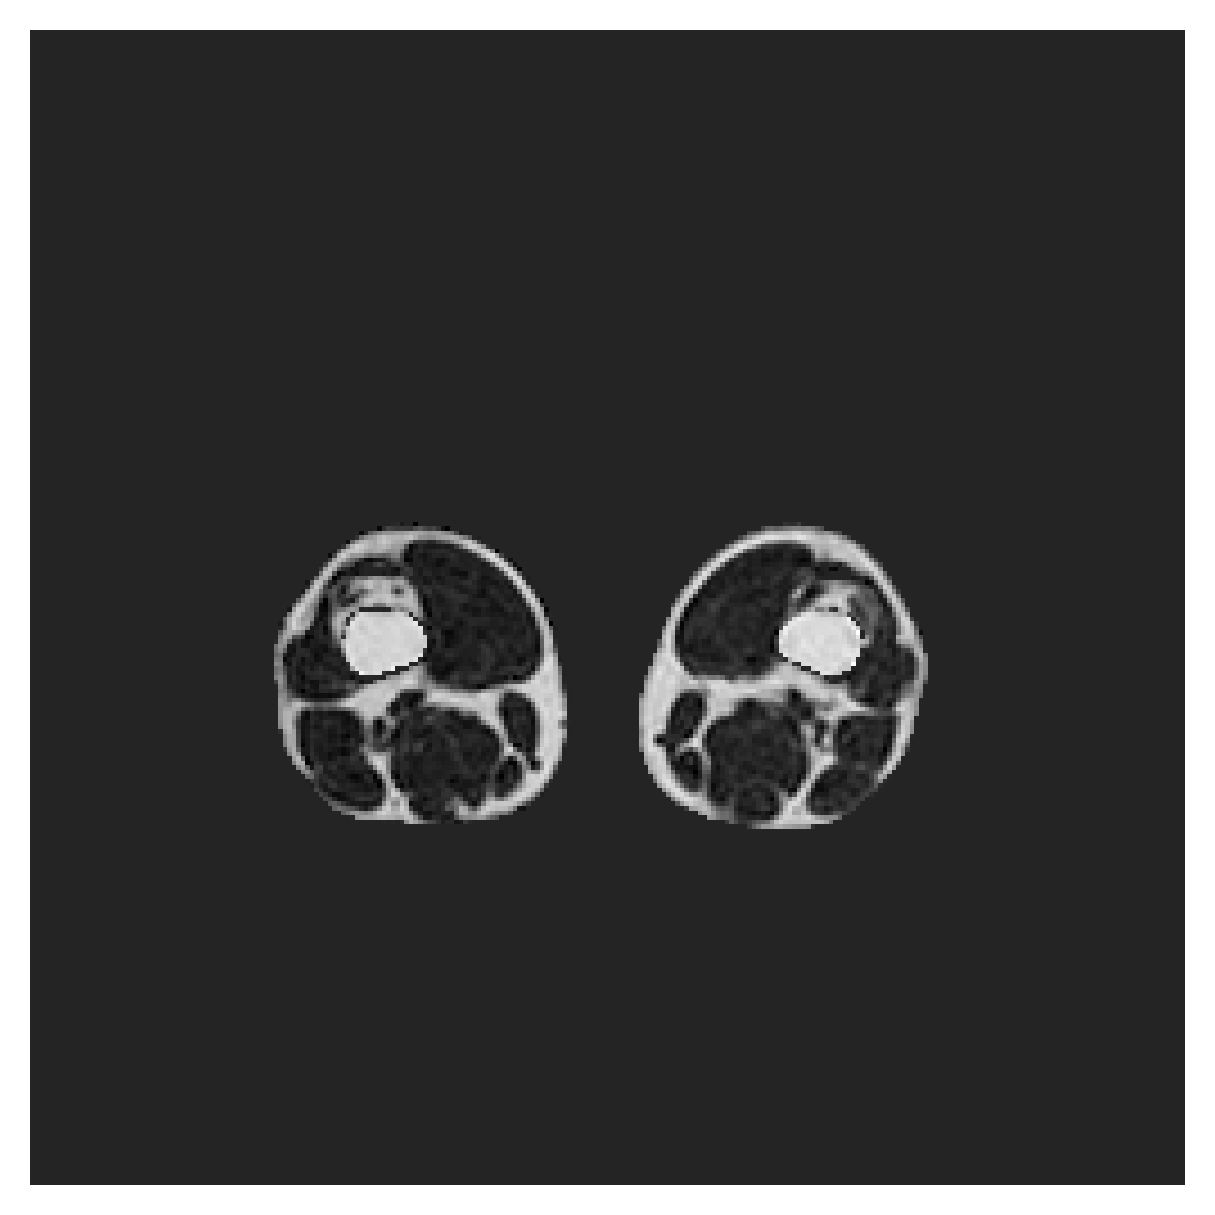

POEM

The Prospective investigation of Obesity, ENergy production and Metabolism (POEM) is a local (not currently publicly available; PI: L. Lind, see [22] for details) cohort of whole-body fat/water separated MR images. Full annotations of the liver, kidneys, bladder, pancreas and spleen are available for 50 subjects, providing a challenging segmentation dataset with heavily imbalanced classes of varying shapes. The resolution of the data is anisotropic, with reconstructed voxel size of in left-right, anterior-posterior and foot-head directions, respectively. For additional technical details regarding the acquisition and specifications of the images see [22].

The images contain two channels, one for water and one for fat content. For training, we normalize the volumes (per channel) and use 2D slices in the coronal plane, sized . The weak annotations are created synthetically, following the same procedure as described for the ACDC dataset.

5.2 Abdominal organ segmentation

Using 2D distance maps

In Table 3, the average DSC and HD95 results are shown (both using 2D and 3D distance maps) for the task of abdominal organ segmentation in POEM data (for boxplots see figures 8 and 9). We see that training with and (with distances calculated on 2D slices) performs comparably, while using and produces lower scores in both DSC and HD95 metric. On this dataset, the CRF-loss is able to compete with the boundary loss-based training strategies, even outperforming them on most classes. Most notably, all models trained with boundary loss appear to have a hard time segmenting the liver. We hypothesize this may be due to extremely severe class imbalance, as the liver covers a very large area compared to the rest of the classes. It is thus also more strongly affected by undersegmentations.

Using 3D distance maps

Inspecting the values of training with on distance maps computed in 3D from Table 3, we notice that the results generally improve over values achieved by using 2D distance maps. Most notable decreases are visible in HD95 values, as using volume-calculated distance maps provides more global information and additionally penalizes spatially unreasonable segmentations. The methods based on are now able to compete with the CRF-loss, in particular the one.

In Figure 10, the validation curve evolution is plotted. Comparing it to the one with using 2D-computed distance maps, in Figure 7, we see that the curves for all the methods training with improve, with the exception of based one. The lack of improvement here could be attributed to the MBD bleeding through object boundaries (due to noise) and propagating low distances further away in the volume, causing under-penalization. This is also suggested by the degradation in performance from 2D to 3D maps in Table 3. But at the same time, it allows for better segmentation of large and/or elongated (homogeneous) objects, which is also confirmed by the large improvement of liver segmentation scores in Table 3.

5.2.1 Qualitative comparison

In Figure 11 and 12 we show the same random slices in cases of calculating the boundary loss on 2D- and 3D-based distances, respectively. Comparing the two figures again indicates that the intensity-aware distances offer most improvement when calculated in 3D over 2D. The exception here is the MBD, which seems to even slightly degrade for most classes.